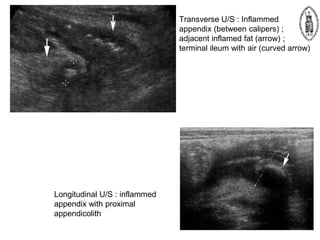

Acute appendicitis

Transverse U/S : Inflammed

appendix (between calipers) ;

adjacent inflamed fat (arrow) ;

terminal ileum with air (curved arrow)

Longitudinal U/S : inflammed

appendix with proximal

appendicolith

 Ultrasound – Advantages •Widely available and inexpensive • Avoidance of ionizing radiation – Especially women of reproductive age and children – Gynecological disease gives further reason for U/S evaluation • Useful in identifying an alternative diagnosis – Disadvantages • Operator dependant – Technique • Graded compression with high frequency linear probe – gradual and constant increase in the compression by the US probe in the right iliac fossa – displaces normal, air-filled bowel, or compresses it against the posterior abdominal wall – abnormal, non-compressible appendix is thus revealed Acute appendicitis

Transverse U/S :Inflammed appendix (between calipers) ; adjacent inflamed fat (arrow) ; terminal ileum with air (curved arrow) Longitudinal U/S : inflammed appendix with proximal appendicolith